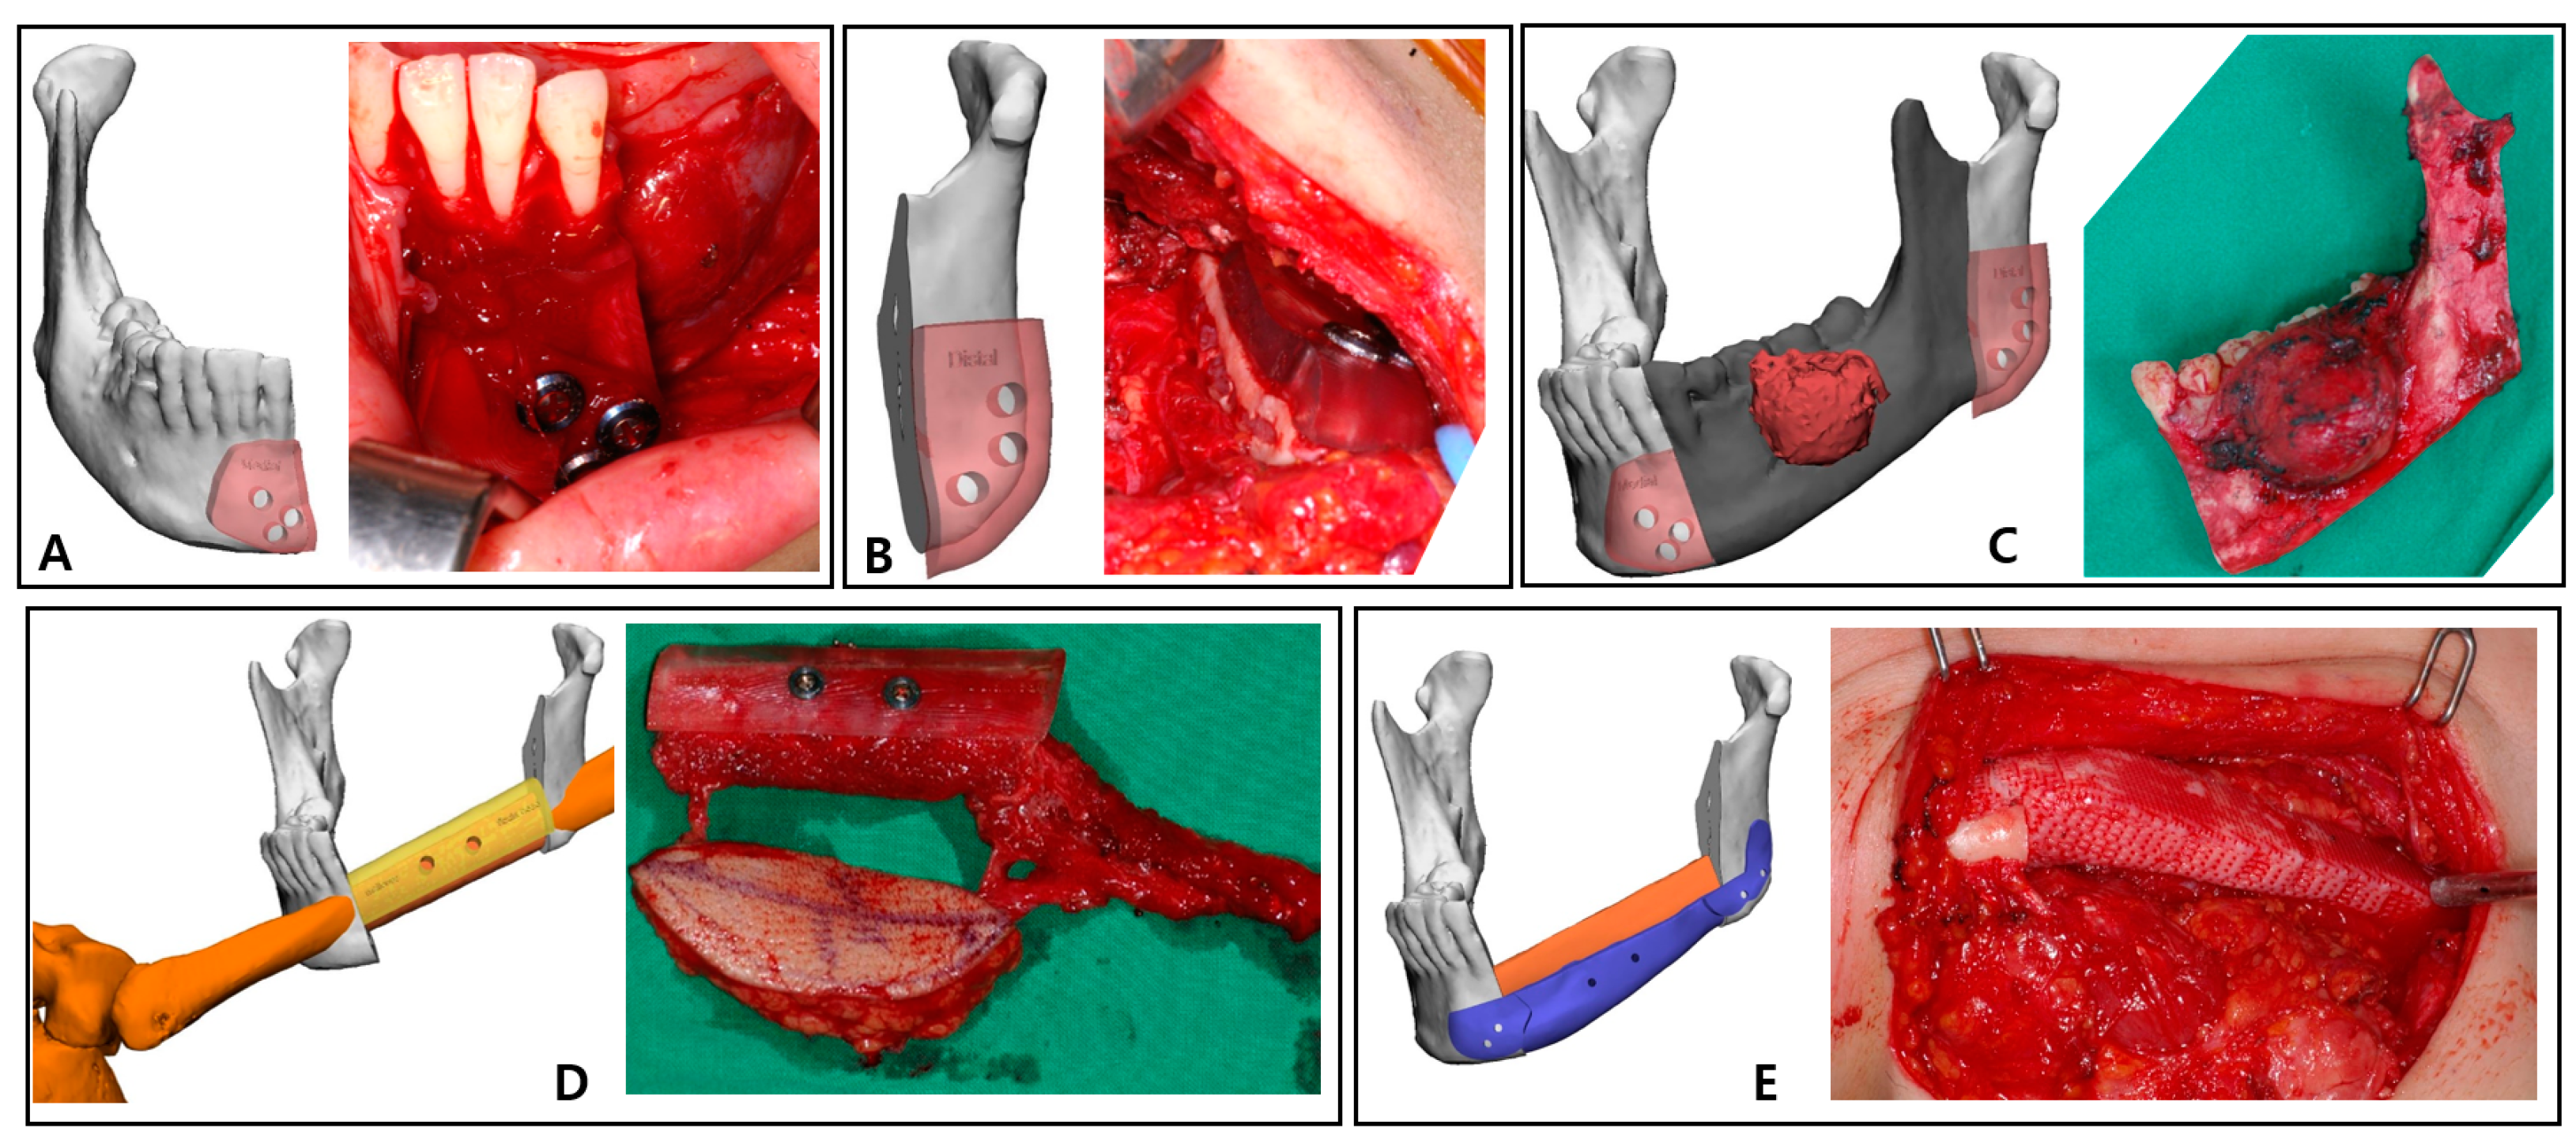

2.3. Surgical Technique

The left mandible and tumor were minimally exposed through simultaneous access to the neck and oral cavity without lip splitting. The transparent mandible cutting guides were adapted to the intended location, drilled in accordance with the fixing holes, and secured with screws (Figure 4A,B). The holes generated in the residual mandible were also planned to be used to attach the PCL implant and the fibula positioning guide in the subsequent process. The osteotomy was completed according to the mandible cutting guides, and the mandibular fragment containing the mass was removed in one-bloc (Figure 4C).

The osteofasciocutaneous fibula free flap with a fusiform skin paddle was obtained from the left lower leg by conventional lateral access. Before separating the vascular pedicle, the fibula cutting guide was precisely positioned on the outer surface of the fibula, drilled along the fixation holes, and monocortically fastened with screws. Then, piezoelectric osteotomy was elaborately implemented according to this fibula cutting guide, and the fibula free flap was harvested (Figure 4D). Immediately after this stage, the bio-printed PCL implant was briefly placed in the extracted fibular space to soak in blood containing bone marrow (Figure 3E).

After placing the fibula segment on the defect of the mandible, the fibula positioning guide was accurately fixed with screws using holes already formed in the remaining mandible and fibula segment. In this state, the fibula segment and the remnant mandible were connected with mini-plates and mini-screws. The positioning guide was eliminated, and the patient-specific PCL implant was arranged below the fibula segment (Figure 4E). This scaffold was also fixed with screws using existing holes of the residual mandible. After microvascular anastomosis in the left neck area, the skin paddle regenerated an oral mucosa, and the neck region was closed.

Figure 4. Intraoperative clinical photographs corresponding to 3D simulation: (A) Right mandible cutting guide fixed with screws; (B) Segmental mandibulectomy performed using the left mandible cutting guide; (C) Tumor resected according to the virtual plan using surgical guides; (D) Skin paddle, peroneal pedicle, and the fibula segment with fibula cutting guide can be seen in the harvest fibula free flap. (E) Three-dimensional-bioprinted PCL implant, with grid pattern recreating mandible border.